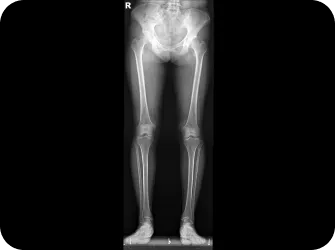

04.

족부

1. 평발은 요통의 위험을 약 4.5배까지 증가시킬 수 있습니다.

2. 요족은 발의 충격 흡수 능력을 저하시켜 보행 시 골반과 허리에 더 많은 스트레스를 줍니다.

3. 비대칭 족부 문제는 보행 패턴을 변화시키고 골반 비대칭을 유발하여 허리 통증을 악화시키는 주범입니다.

※ 허리 통증 치료 시 발의 상태를 함께 확인하고 교정하는 것이 매우 중요합니다. 발 교정을 통해 올바른 체중 분산과 보행 패턴을 만들어주면 허리 건강 개선에도 큰 도움이 됩니다.

• 다리 길이에 차이가 있다.

똑바로 누운 상태에서 양쪽 다리 길이를 잽니다.

(다리를 일부러 비뚤게 놓거나 자세가 나쁘면 정확한 측정이 곤란)

한 쪽 다리가 짧다면 골반이 비뚤어졌거나 척추가 불안정한 상태입니다.